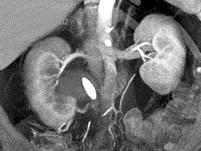

男,27岁,请根据所示图像,选择最可能诊断 ( )A、右肾结石B、右肾钙化C、右侧肾盂结石D、右侧肾盂癌E、右侧肾盂血块

问题 男,27岁,请根据所示图像,选择最可能诊断 ( )

选项 A、右肾结石 B、右肾钙化 C、右侧肾盂结石 D、右侧肾盂癌 E、右侧肾盂血块

答案 C